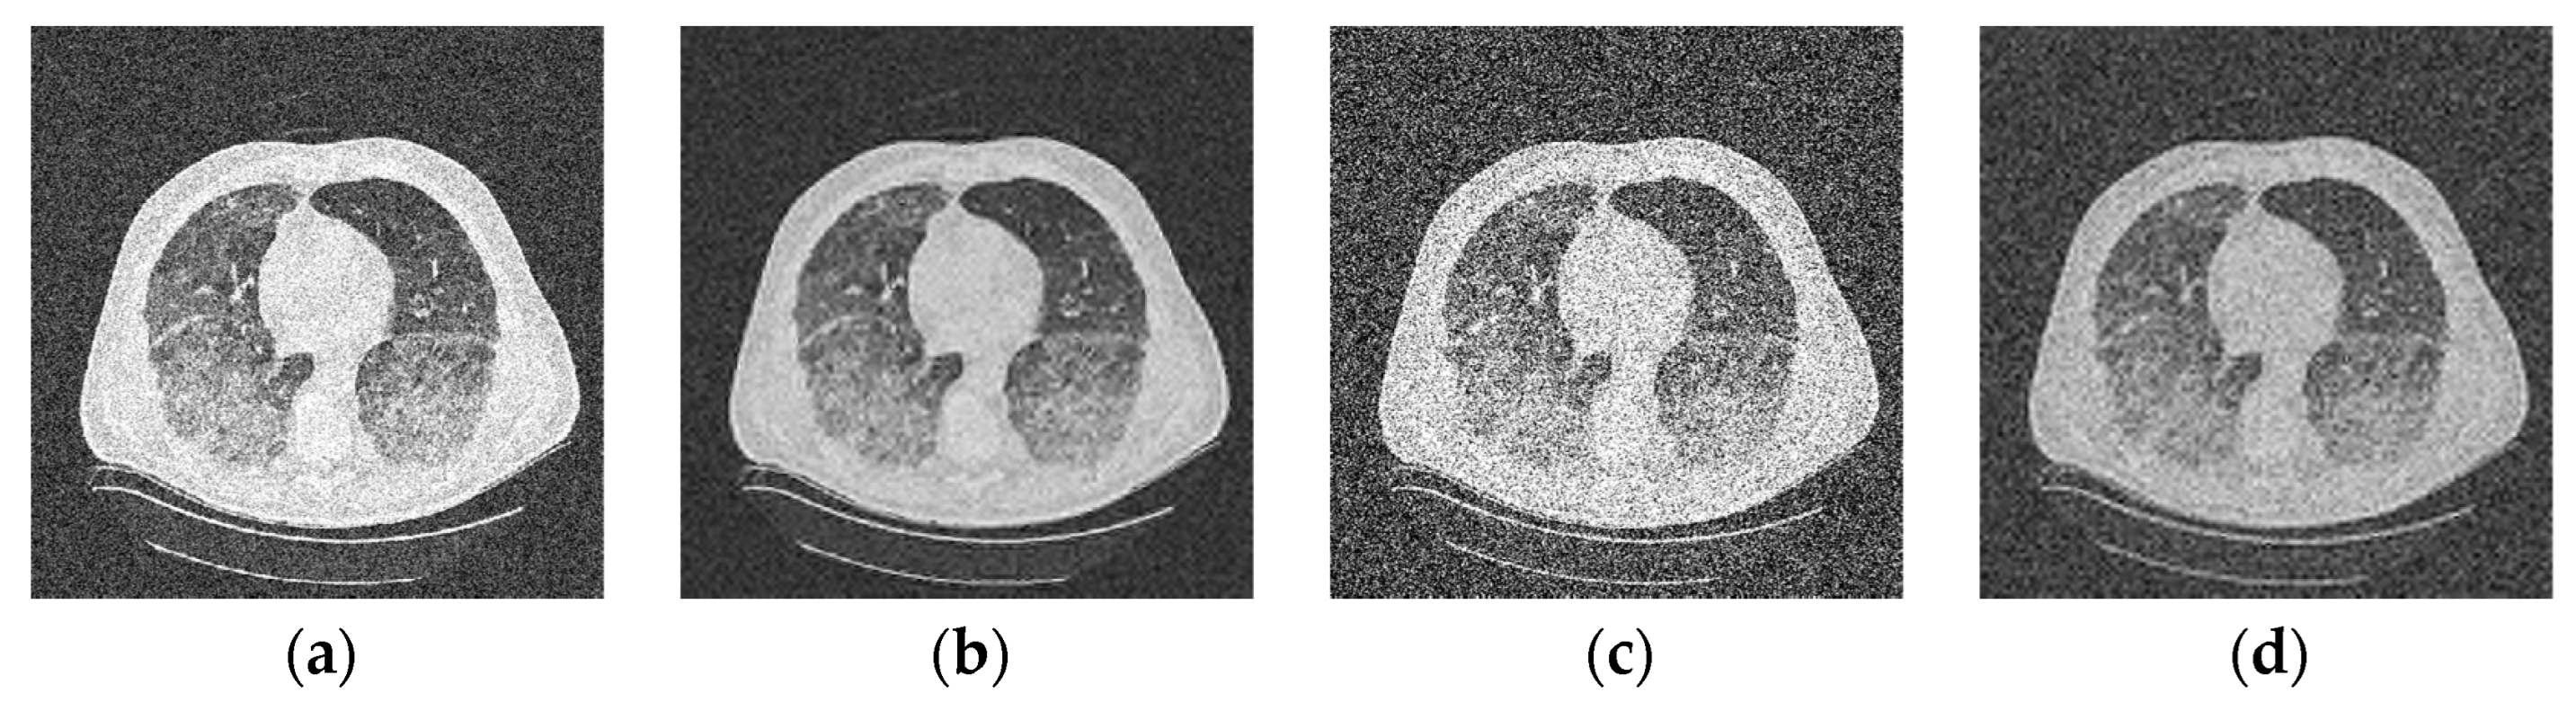

4. Experiment

5. Discussion